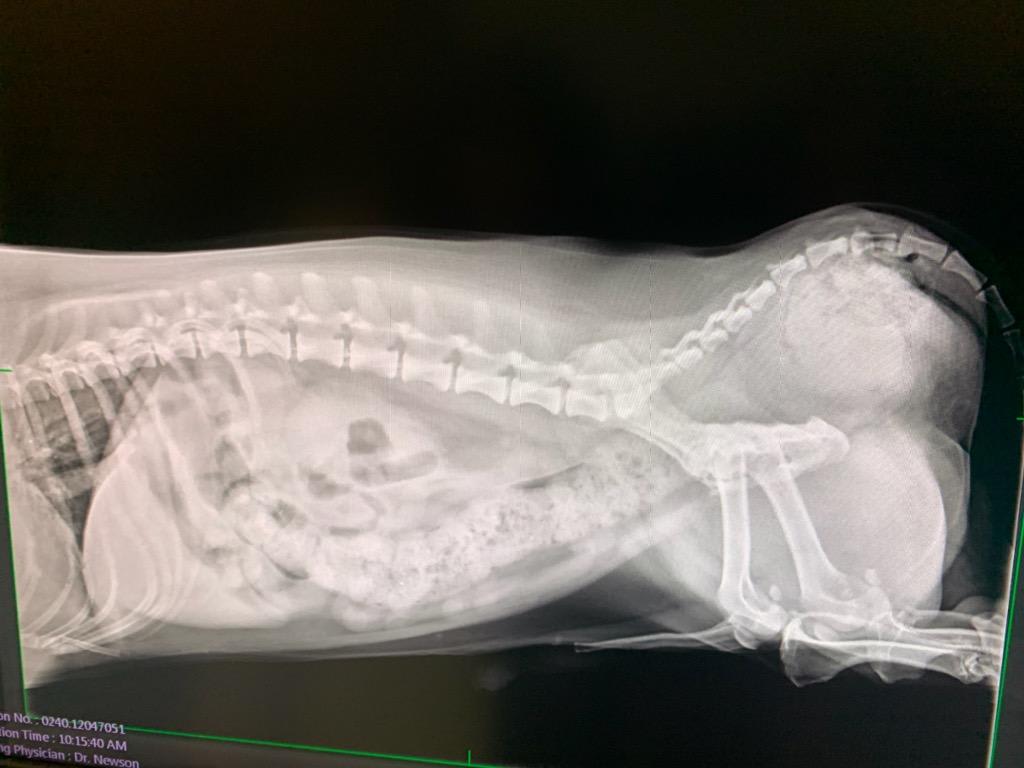

Long story short. My dog has a pernieal hernia and needs surgery ASAP. His bowls are blocked and his urinary tract is out of place. I am working on getting the $3000-$5000 that is needed to cover the cost of surgery. In the mean time would I take him in to another clinic or ER so he can relieve himself via cath and also see if they can give him something for pain?